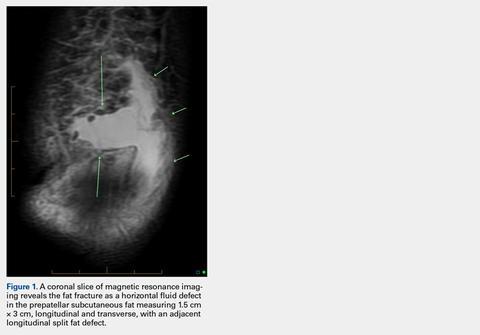

These findings were consistent with a localized “fat fracture.” There was an associated, 2 cm × 6 cm, sagittal and coronal/longitudinal, medial prepatellar bursal fluid complex and subcutaneous edema adjacent to the fat fracture (Figure 3). However, the patellar and quadriceps tendons were intact. A 12-mm focus of marrow edema at the superior pole of the patella was consistent with a contusion.